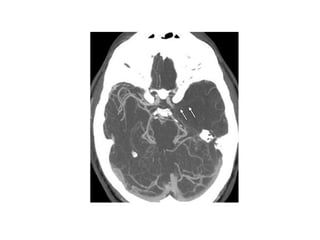

CT Angiography

and

CT Perfusion

• For assessment of intracranial and extracranial

circulation

• Can demonstrate thrombi

• Timed bolus of contrast for vessel enhancement

• Can guide decision regarding intraarterial or mechanical

thrombolysis by quantifying clot burden